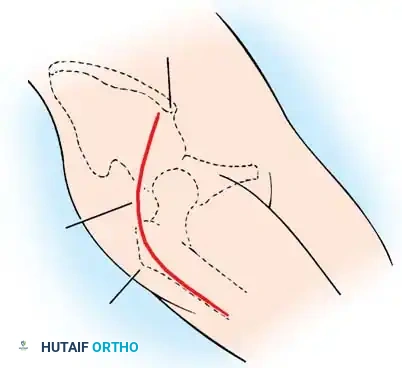

Anterior Approach (Smith-Petersen):

1. Incision: "Bikini" incision below the iliac crest.

2. Interval: Develop the plane between the tensor fasciae latae (superior gluteal nerve) and the sartorius (femoral nerve).

3. Deep Dissection: Detach the rectus femoris from the AIIS. Isolate and release the iliopsoas tendon at the pelvic brim to relieve the hourglass constriction of the capsule.

4. Capsulotomy: A T-shaped or I-shaped capsulotomy is performed parallel to the acetabular margin.

5. Joint Clearance: Excise the ligamentum teres, clear the pulvinar, and incise the transverse acetabular ligament inferiorly. Never excise the limbus, as it is critical for future acetabular growth; radial incisions may be made if it is severely inverted.

6. Capsulorrhaphy: Following concentric reduction, the redundant capsule is advanced superiorly and laterally to stabilize the joint.

Intraoperative view of the anterior approach to the hip, demonstrating capsulotomy and exposure of the dysplastic joint.